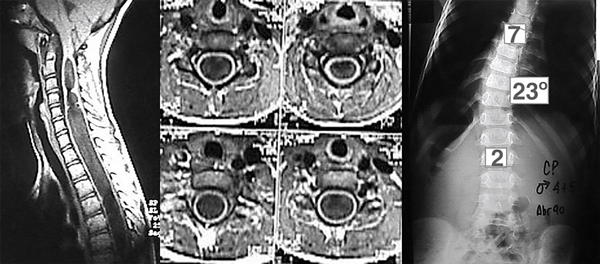

Paciente masculino de 4 años y 6 meses con ausencia de reflejos cutáneos abdominales y una escoliosis torácica de convexidad izquierda, cuyo valor angular de Cobb T-L3 de 230° y convexidad izquierda se trató con corsé toraco-lumbosacro (tipo TLSO). La RM mostró una malformación de Chiari tipo I asociada a una extensa siringomielia, desde C2 a T9 (Figura 1). Los potenciales evocados somatosensoriales (PESS) resultaron normales. Se adoptó conducta expectante.

Figura 1. Cortes sagital y axiales en los que se observa extensa dilatación siringomiélica. Espinograma, frente.